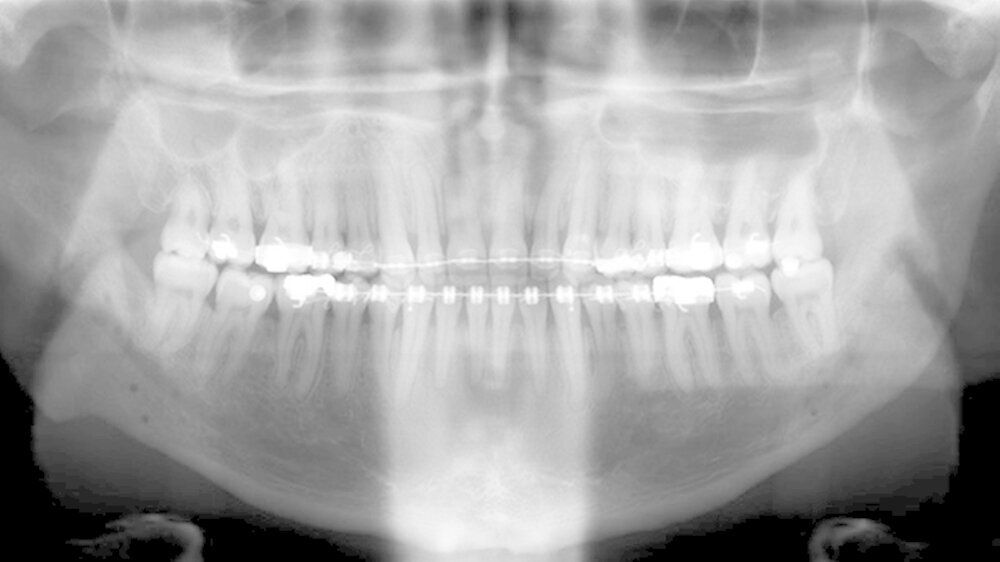

Der Patient stellte sich erstmals 2010 in der Stuttgarter MKG-Spezialsprechstunde vor. Im ersten Schritt wurde der Tumor an der Hirnanhangdrüse über die Nase entfernt. In interdisziplinärer Zusammenarbeit mit einem Fachzahnarzt für Kieferorthopädie wurden im ersten Behandlungsabschnitt die Zahnbögen ausgeformt. Um den Oberkiefer in der Breite zu dehnen, führten die Stuttgarter Zahnärzte im Oktober 2012 eine chirurgisch unterstützte Gaumennahterweiterung durch.

Nach dreidimensionaler Planung im zahntechnischen Labor, in dem die Bissschlüssel konventionell hergestellt wurden, wurden dann ein Jahr später beide Kiefer operativ mobilisiert. Hierzu wurde von einem Schnitt im Mund der Oberkieferknochen freigelegt.

Mit einer Säge wurde ein gezielter Knochenschnitt durchgeführt. Nach der Präparation wurde der zahntragende Abschnitt des Oberkiefers vom restlichen Gesichtsschädel gelöst. Erst wurde die Bisssituation anhand des Bissschlüssels exakt eingestellt, dann mit 2 mm dicken Osteosyntheseplatten aus Titan der Knochen in der neuen Position mithilfe von Titanschrauben fixiert.

Im Unterkiefer erfolgte dann die Schnittführung im Zahnfleisch hinter dem letzten Backenzahn beidseits. Nun wurde der Unterkiefer mit spezieller Technik durchtrennt um die zahntragende Basis vom gelenktragenden Knochenabschnitt des Unterkiefers zu verschieben. Bei der Präparationwurde der im Unterkieferknochen verlaufende Gefühlsnerv der Unterlippe sorgfältig geschont.

Die neue Position wurde mit einem zweiten Bissschlüssel, der die endgültige Bisssituation einstellt,zugeordnet und mit Osteosyntheseplatten und -schrauben gesichert. Die Operation ging mit einem stationären Aufenthalt von nur fünf Tagen einher.

Das deutlich harmonischeres Profil drei Monate nach der Operation: Im Mai des nachfolgenden Jahres wurden die Metallplatten in einem ambulanten Eingriff wieder entfernt. Eine Multibandapparatur hält die Zähne noch "in der Reihe". Der Patient kann heute dank der individuellen innovativen Behandlung ein normales Leben führen, die Gesichtsästhetik und seine Kaufunktion sind vollständig wiederhergestellt.